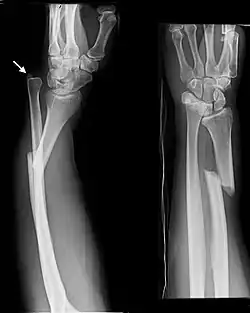

Galeazzi fracture

The Galeazzi fracture is a fracture of the distal third of the radius with dislocation of the distal radioulnar joint. It classically involves an isolated fracture of the junction of the distal third and middle third of the radius with associated subluxation or dislocation of the distal radio-ulnar joint; the injury disrupts the forearm axis joint.[1]

The dislocation of ulnar head in Galeazzi fracture dislocation may be dorsal (commoner) or volar (rare) depending on the mechanism of injury. If the fall is on the outstretched hand with forearm in pronation, the dislocation is dorsal, and if forearm is in supination at the time of injury, the dislocation is volar.[2]